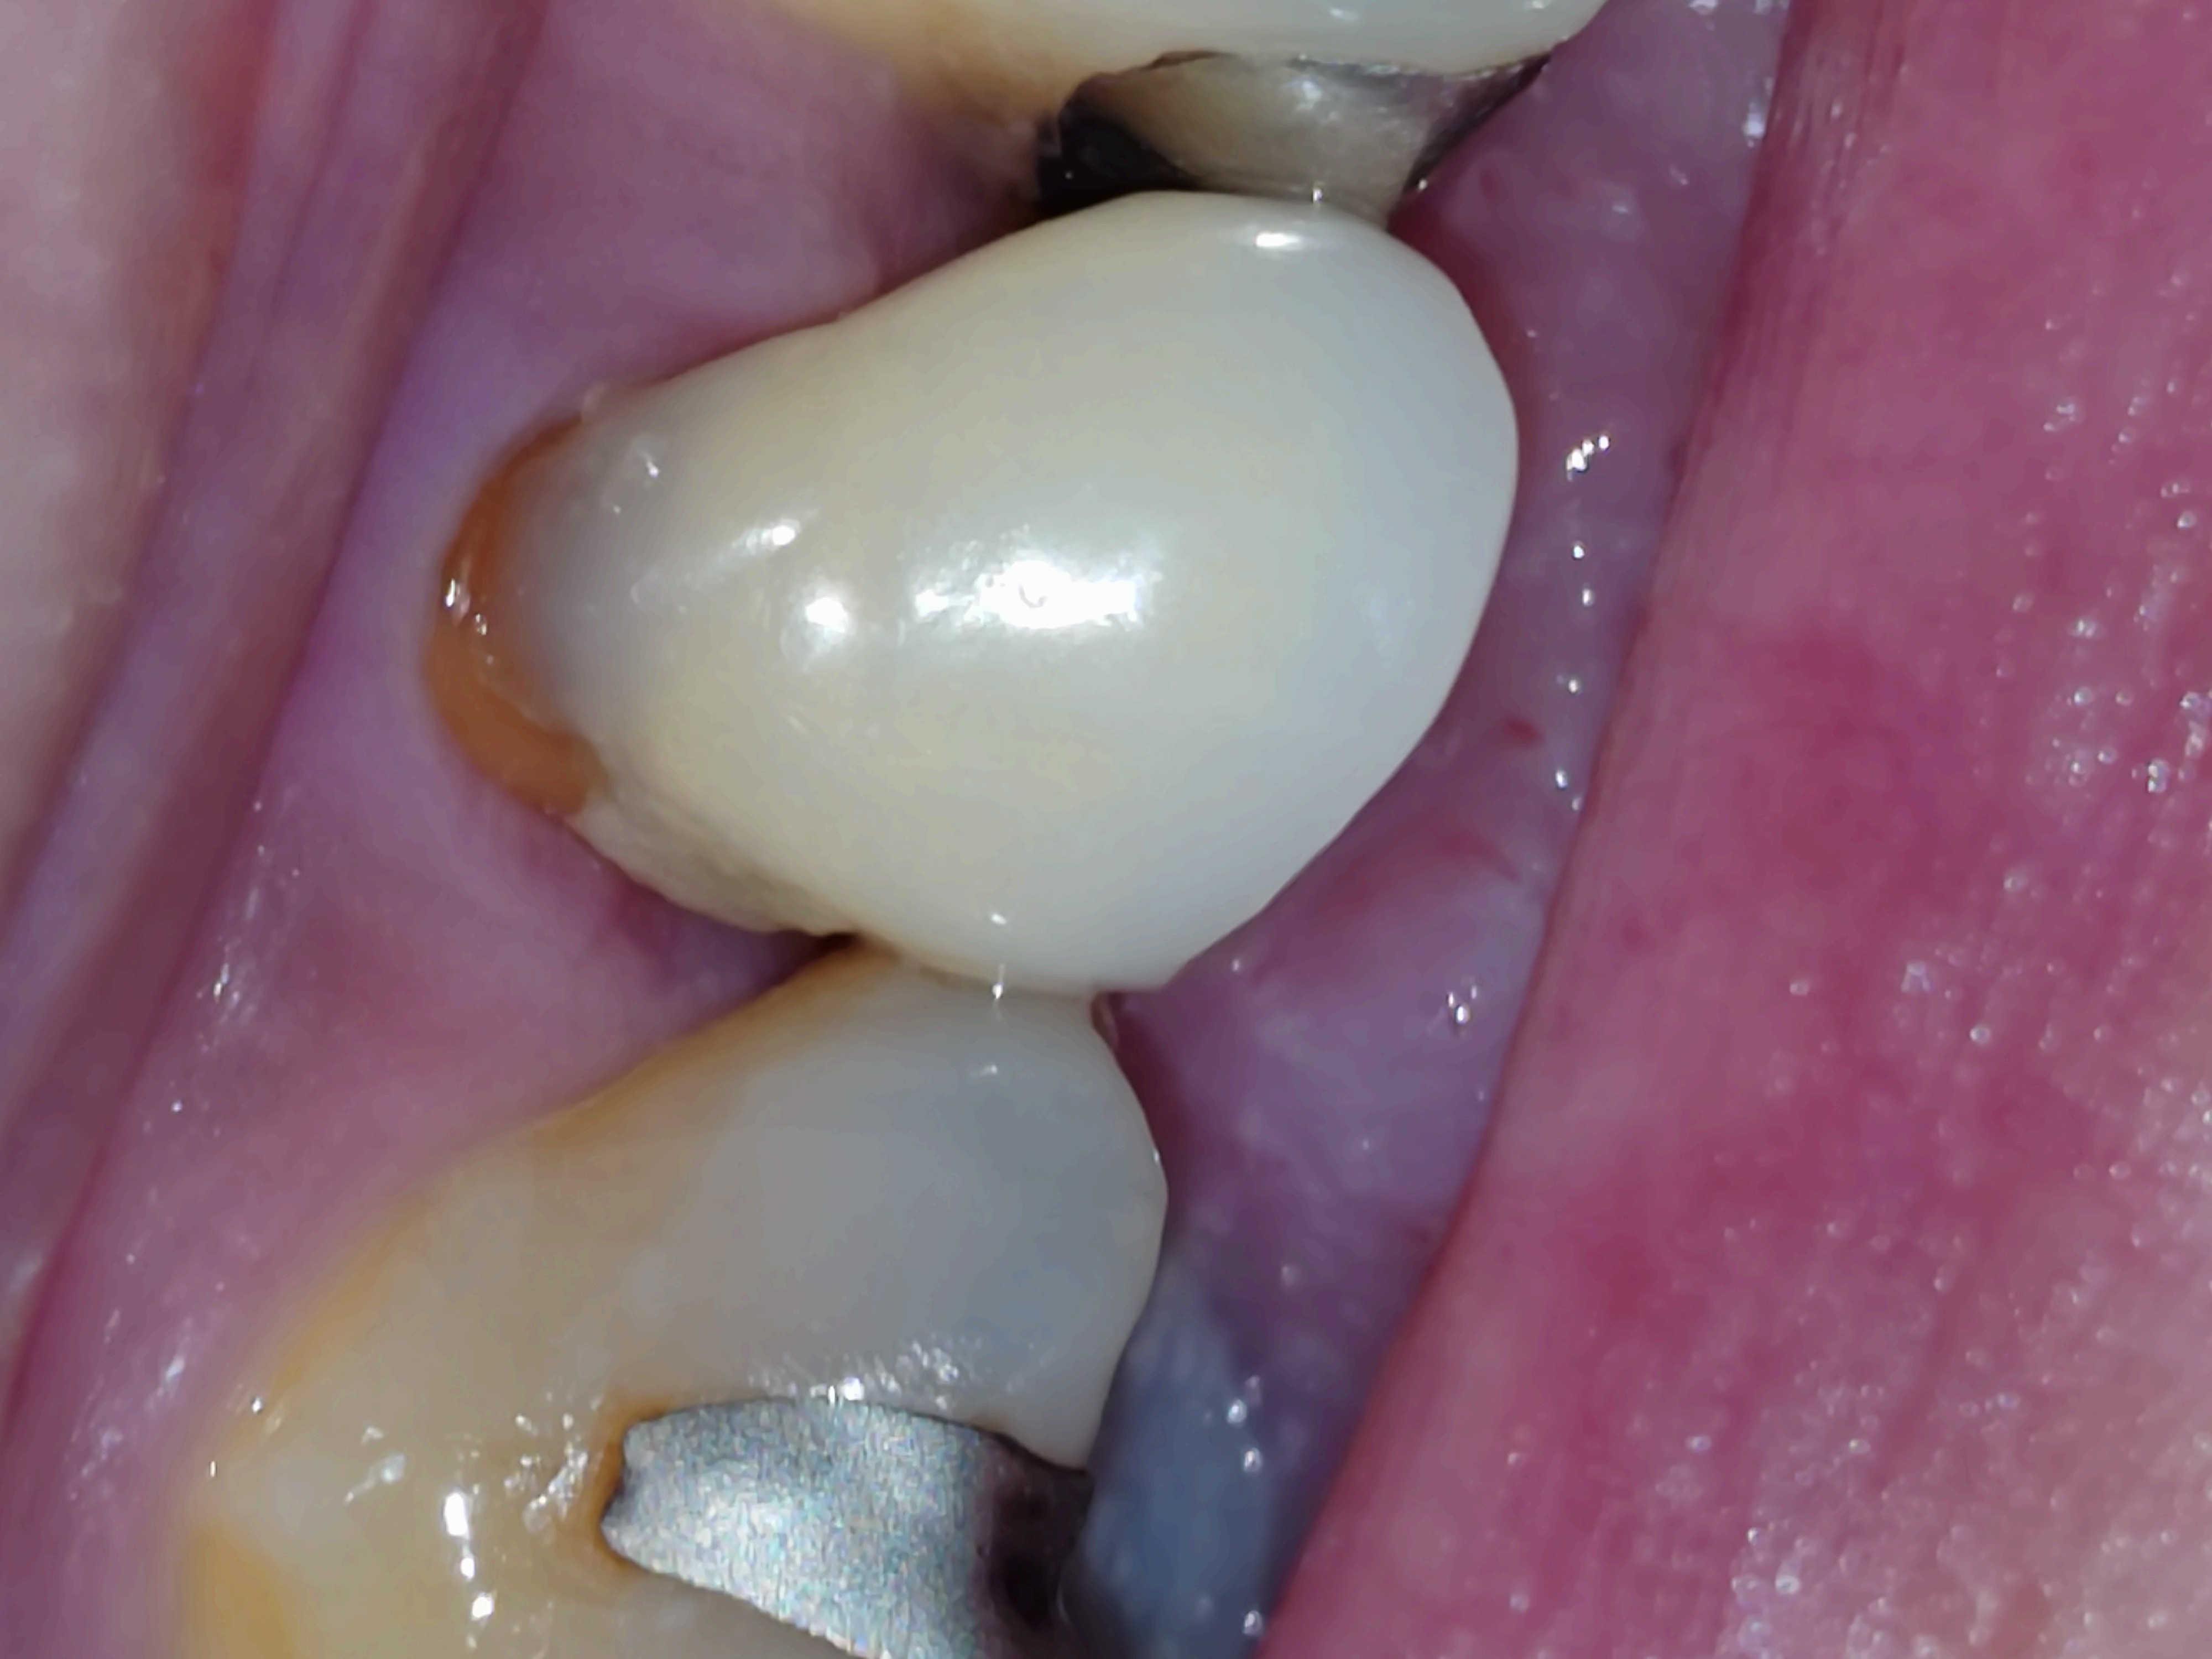

古いものでしたので歯茎との境目に土台が見えており、先生が良かれとレジンを流されたのですがとても雑な感じです。

近心は足りない感じで、遠心歯茎を持ち上げるようにレジンが乗っていたりレジンを流されていない所が(涙型)あったりします。

研磨は一切せず、ザラザラ凸凹です。